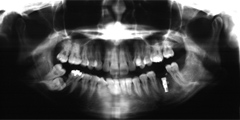

吉本歯科医院では、口内写真とパノラマレントゲンを撮影し、まずは顎の骨の状態まで詳しく確認しました。

(写真(1))虫歯の進行により歯の根っこに膿ができ、歯の周辺の骨まで溶け出している

正確な診断

院長の吉本の診断は、次の2つでした。

・虫歯の進行により、歯の根っこに膿ができ、歯の周辺の骨までごっそり溶けてしまい歯がグラグラと揺れだした。

・親知らずを放置していたことにより、健全な歯を横に押し出し全体の噛み合わせ(咬み合わせ)のバランスを崩し、歯並びが悪く、不自然な力で噛み続けていたため歯が揺れだした。

写真(1)

骨が無い部分にGBR(骨再生手術)を行い、インプラントと骨をくっつける